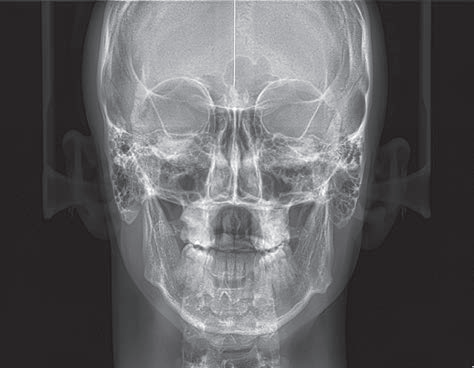

Hyperion X5全景、头颅和X射线体层摄影设备

Hyperion X5不断进化发展,现在头颅及3D拍摄也来到您的面前。这边在整个拍摄过程中快速易用,确保了高分辨率的3D和2D图像、低辐射时间以及实时诊断所需的快速数据处理,改善医患沟通。新的虚拟控制面板简化了拍摄流程,并引入了上颌窦容积检查和正交全景图像的新程序。由于3D传感器模块的自动伺服控制运动,较短的检查时间确保了连续的愉快体验。